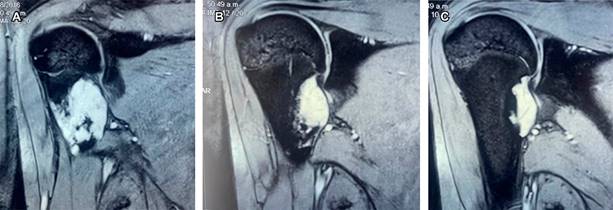

Las radiografías muestran una lesión exofítica con continuidad corticomedular con el hueso adyacente (Figura 1), con base de implantación sésil o pedunculada. La ecografía visualiza la capa cartilaginosa como un área hipoecoica sobre la corteza ósea, la tomografía computarizada (TC) permite visualización de la continuidad corticomedular de la lesión (Figura 2), la resonancia magnética (RM) es de elección para valorar las estructuras circundantes a la lesión, la capa de cartílago no mineralizada muestra señal alta en T1 y T2 (Figura 3). La resección está indicada al final del crecimiento.

Figura 3: Imágenes de resonancia magnética de hombro derecho, ponderadas en T2, que muestra señal alta en cara anterointerna de metáfisis correspondiendo a zona cartilaginosa de osteocondroma en adolescente de 17 años, ejerciendo presión sobre conducto neurovascular de Cruveilhier.